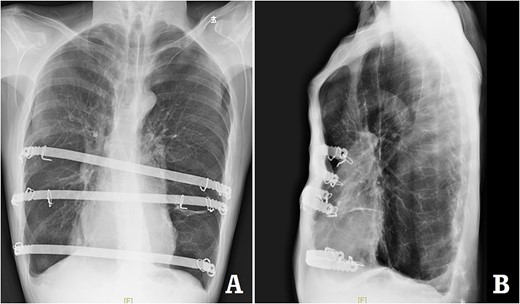

The patient was a 29-year-old male. He was found to have protrusive deformity on the anterior chest wall since childhood. The deformity was not serious in early years, but worsened after adolescence, with the lower part of the sternum protruding at an acute angle. At the age of 25, he developed right spontaneous pneumothorax and received surgical treatment at local hospital, but his thoracic deformity was not treated. As the deformity continued to worsen, which seriously affected the appearance of the chest wall, the patient was admitted to our hospital for surgery. Preoperative physical examination showed that the anterior chest wall was protrusive seriously, with a sharp tip protruding forward. The rib arches on both sides were slightly depressed (Fig. 1). Imaging examination showed that the anterior chest wall was protrusive, and the lower end of the sternum was at the forefront of the protrusion. His heart moved to the right, and the rib arches were slightly depressed (Figs 2–4). The operation was performed under general anesthesia. Two longitudinal incisions were made on both sides of the chest wall respectively. The incisions were located between the front axillary line and the median axillary line, with the length of ~5 cm. The chest wall muscles were dissected to expose the ribs in the incisions. Two tunnels were made on the highest plane of the protrusion, with interval of 3 cm. The tunnels were located in the deep layer of the chest wall muscles and bone structures. Two steel bars were inserted into the tunnels to flatten the front protrusion with their median parts, and then, both ends of the steel bars were fixed on the ribs at the lateral chest wall. The above operation was the main content of Wenlin procedure [1, 2, 5]. After this procedure was completed, the lower part of the chest wall showed obvious depression, especially in the middle of the rib arches. Then, Wung procedure was performed [6]. A third tunnel was made at the plane passing the midpoint of the rib arch, which passes through the bilateral thoracic cavity. The third steel bar was inserted into the tunnel. After the steel bar was rotated and fixed to the ribs, the depression was supported totally. The incisions were closed, and the operation was completed. The deformity of anterior chest wall disappeared completely after the operation (Fig. 5). The operation time was 75 min. The intraoperative bleeding volume was 40 ml. Postoperative X-ray examination showed that the bars position was normal (Fig. 6). He was discharged 7 days after operation. Follow up for 1 year showed satisfactory recovery. The steel bars were taken out 1 year after the operation, and the appearance of the thorax was normal and there was no recurrence (Fig. 7).

X-ray examination after the bars were taken out. (A) Posteroanterior radiograph; and (B) lateral radiograph.